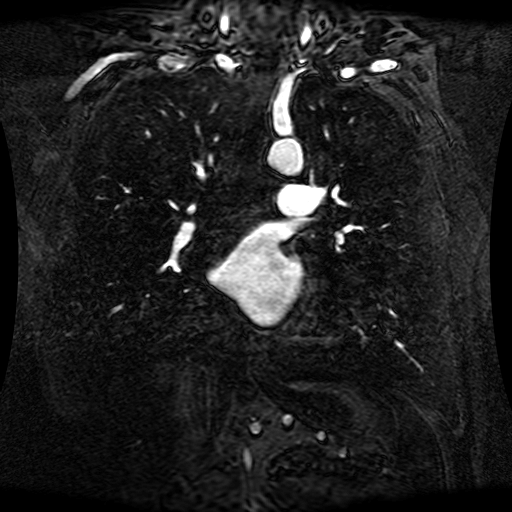

These magnetic resonance angiography (MRA) images show coronal slices acquired from consecutive anteroposterior positions within the torso. The study was performed on a 1.5T General Electric (GE) Signa imaging system with gadolinium-contrast-enhancement for visualization of the cardiopulmonary vasculature. The pulse sequence used was a 3D time-of-flight fast spoiled gradient recalled acquisition in steady state (FSPGR, TR=6.3, TE=1.4, NEX=1, FOV = 40cm, slice thickness = 1.2mm).

This sample image contains 76 frames. It is available in DICOM format (E1154S7I.dcm), as an animated GIF (E1154S7I.gif), as .ogg, .mp4, .webm, and .swf animations (one of which is shown above), or as individual PNG-format frames (see below).